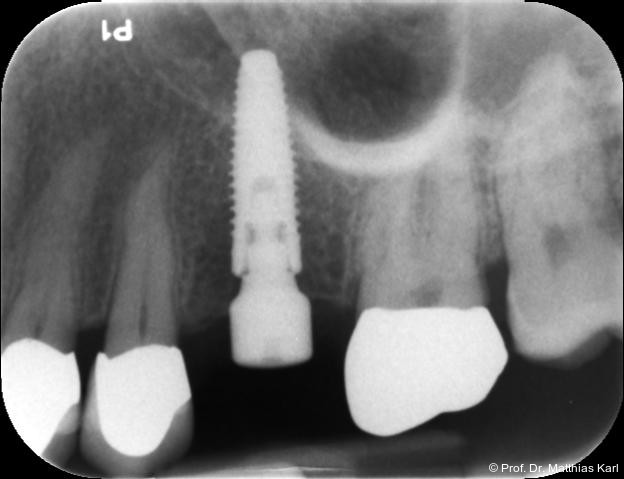

Ein wesentlicher Parameter für den Erhalt der Funktion und Ästhetik zahnärztlicher Implantate ist der Zustand des periimplantären Knochens,17 weshalb dessen Niveau relativ zur Implantatschulter kontinuierlich röntgenologisch überwacht wird. Der periimplantäre Knochenverlust gilt nach wie vor als entscheidendes Erfolgskriterium. Grenzwerte für den Knochenverlust sind dabei auf 1 mm im ersten Jahr nach der Implantation festgelegt, gefolgt von maximal 0,2 mm jährlich in den folgenden Jahren.2, 6, 19

Die höhere initiale Verlustrate des periimplantären Knochens wird primär auf das chirurgische Trauma zurückgeführt, bei dem auch die Kompression des Alveolarknochens während der Implantatinsertion eine Rolle spielt. Der nachfolgende Knochenabbau während der Implantatlebensdauer wird derzeit als eine Fremdkörperreaktion beziehungsweise als Anpassung an die spezifische Belastungssituation verstanden, im Gegensatz zu einer entzündlichen Periimplantitis.3

Zur Reduktion der Knochenkompression, insbesondere der bukkal gelegenen Lamelle (Abb. 3), werden derzeit Implantate mit dreieckigem Querschnitt10, 12 sowie Implantate mit zervikal reduziertem Durchmesser16 angeboten. Diese scheinen jedoch im Gegensatz zur subkrestalen Positionierung (Abb. 4a–c) von Implantaten23 keine signifikanten Vorteile zu bieten. Bohrprotokolle, welche sowohl auf das jeweilige Implantatsystem als auch auf die vorliegende Knochenqualität abgestimmt sind, haben ebenfalls das Ziel, zu hohe Einbringdrehmomente zu vermeiden.